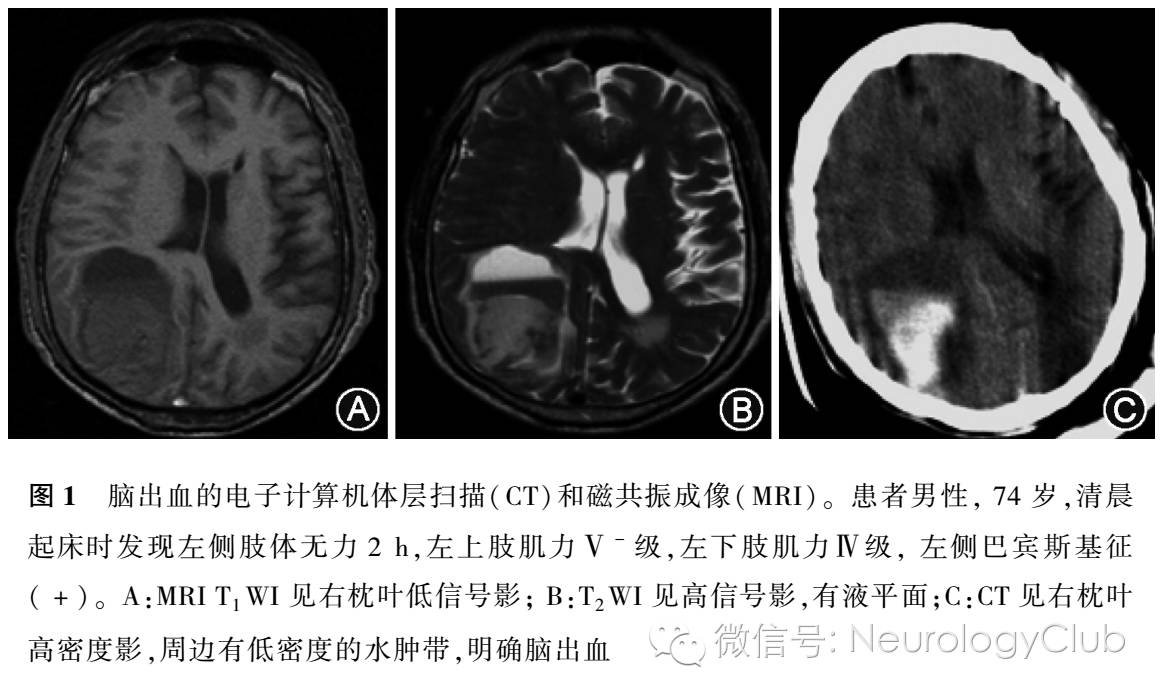

NCCT因其检查时间短、扫描速度快、不受金属器械及移植物影响等优势,可确定出血部位,估计出血量,判定出血是否破入脑室,并判断有无脑疝形成,是目前临床确诊急性脑出血的首选方法(图1),也是急诊鉴别缺血性卒中和出血性卒中、溶栓前排除脑出血最常规的筛查方法。NCCT可以显示直径>5mm呈高密度区的急性脑出血。急性期颅内出血,NCCT呈高密度,系血液中血红蛋白密度高于脑组织密度所致,多为圆形或卵圆形。约24h后,高密度血肿周围常有一低密度环存在,由于血肿周围的水肿和析出的血浆,通常在出血第5天最明显。随着时间的推移,NCCT上的特征性高密度影逐渐减弱、消失,大约在8-10d后变为低密度影,通常出血1个月时,整个血肿呈等密度或低密度。

目前,NCCT是临床上公认的急性缺血性脑卒中的常规检查和首选检查手段。表现为低密度影,但在早期不一定都能显示低密度改变,故其重要作用是排除脑出血。在组织纤溶酶原激活物(tissue type plasminogen activator,t-PA)溶栓前采用NCCT排除颅内出血,是简便快捷的有效方法。在部分患者卒中超急性期(<6h),NCCT可表现为灰质与白质分界消失,在溶栓时间窗内的检出率低于67%;急性期(<3d)可出现血管源性水肿,在缺血区的边界显示欠清低密度影,病灶局部会出现脑沟、脑裂变浅,大面积梗死则可因脑水肿而出现占位效应,从而出现中线结构的移位;亚急性期(<2周)即模糊效应期;慢性期(1-2个月),由于病灶液化坏死,边界清楚的软化灶形成,而呈现出低密度影,病灶局部周围脑沟、脑池增宽,邻近脑室扩大,局部脑萎缩。NCCT对急性缺血性脑卒中的敏感度取决于梗死灶的影像特点、临床检查的时间、研究人群以及其他因素,敏感度约为12% -92%,通常起病24-36h 才出现低密度改变。美国神经病学会报道, NCCT对早期的脑梗死诊断的敏感度为31%。而NCCT对脑梗死早期征象(early ischemic changes,EICs)的探讨一直是研究的热点,是否对溶栓治疗有预测价值存在争议。EICs包括以下几点:(1)高密度的大脑中动脉/基底动脉征;(2)脑沟消失;(3)基底节/皮质下低信号;(4)皮质灰质白质界限消失。美国国立神经疾病和卒中研究所的NINDS研究发现EICs与卒中严重程度有关,而与溶栓治疗的不良预后无关。在2005年Wardlaw和Mielke的一项系统回顾性研究发现,来自15项研究的3468例患者中,早期CT征象检出的敏感度和特异度分别为66%和87%,但未发现相关证据证实其与溶栓结果存在相关性。EICs总分10分[Alberta早期CT评分(ASPECTS)],Dzialowski等从欧洲-澳大利亚急性卒中研究(ECASS II)数据中对ASPECTS与溶栓预后相关性进行了研究,发现ASPECTS与t-PA溶栓效果不相关,但ASPECTS≤7分与溶栓相关的脑实质出血密切相关。大脑中动脉高密度影(hyperensemiddle cerebrl artery sign,HMCAS)可作为NCCT早期征象的特异性表现,往往提示脑梗死面积大,预后不佳。HMCAS与静脉溶栓后治疗效果不佳相关,提示早期即有神经损害以及功能缺损较严重。

MRI对于脑出血的诊断敏感度主要取决于出血时间及扫描序列,主要与血管内红细胞的完整性及血红蛋白的演变有关。MRI在脑出血急性期、亚急性期及恢复期T1WI和T2WI均有不同程度的表现,但是由于缺乏特征性的表现,不建议用于早期脑出血的诊断。梯度回波成像技术通过检测脱氧血红蛋白这一顺磁性物质在磁敏感序列梯度回波T2WI像上的显像,可以在急性期观察到低信号区内混杂斑块状信号,用于脑出血的早期诊断。近期研究发现MRI和CT对诊断急性脑出血的准确率均为96%,肯定了梯度回波序列对脑出血诊断的高敏感度和高特异度,与CT比较,还能检测到微出血病灶,获得更多的出血征象。